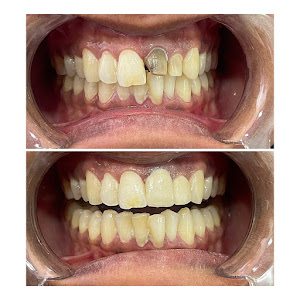

Welcome to our gallery

See how our company transforms ideas into reality. This gallery is a visual testament to our work and achievements.